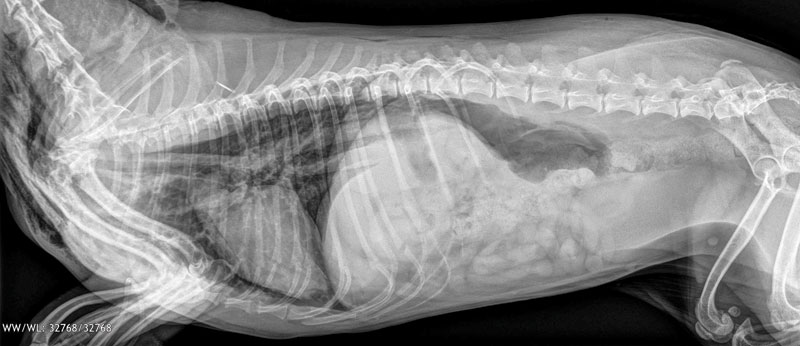

The holidays are supposed to be a time of joy, and sometimes pets try to get in on the festivities, too -- ones they shouldn't! This infographic reminds clients which foods and decorations are naughty and which are nice. Feel free to post these holiday hazards in your waiting room, on your socials, or use as an email blast to clients!

Christmas and Hanukkah hazards infographic download

Download and post this handy guide as a reminder for your clients